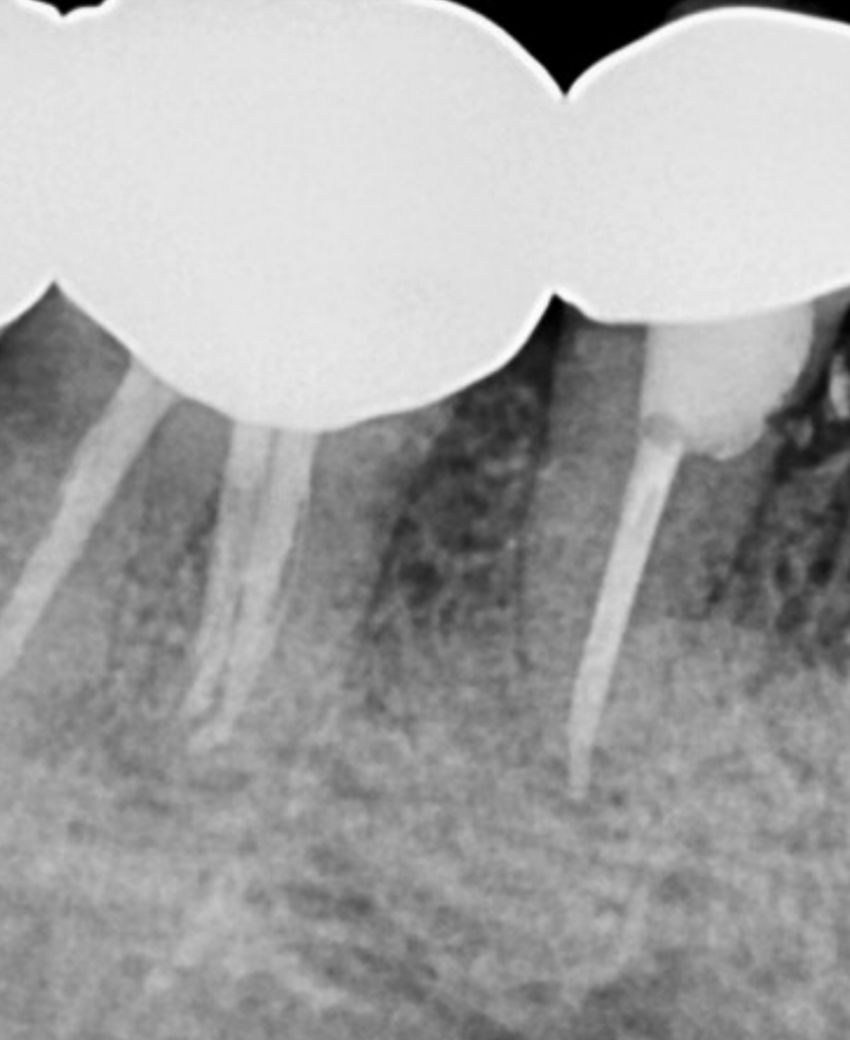

이건 (밑으로)3일전 엑스레이

혹시 염증이 재발한걸까요 아니면 낫는 과정이라 음영이

보이는 걸까요??

사진에서는 특별히 문제될 것은 없어보이며 지금 치과를 바꾼다고 나을지도 확신은 없습니다.